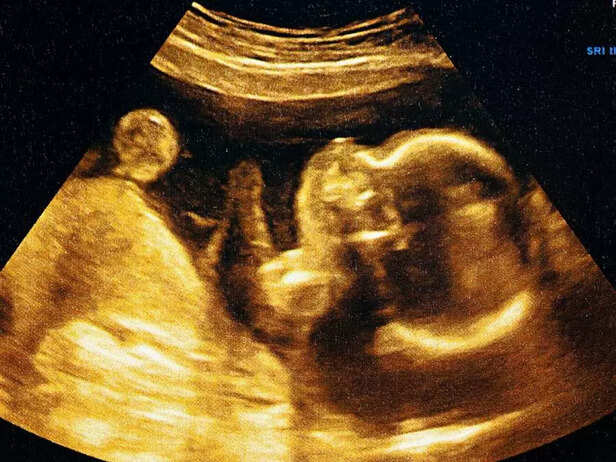

![BABY SONOGRAPH]()

1. Embryo Development at Week 6

By week 6, your baby has grown from an embryo to a fetus. This beautiful transition marks the beginning of big changes in your baby's physical appearance and overall development. The tiny creature within you, no larger than a pea, now has a beating heart and rapidly developing body systems.

2. Formation of Facial Features

During week 6, the early formation of your baby's facial features becomes evident, even though they are still in their early stages.